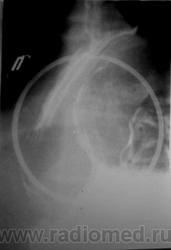

Наблюдение Морозова А.И. Фиксированная параэзофагеальная грыжа пищеводного отверстия диафрагмы

Фиксированная параэзофагеальная грыжа пищеводного отверстия диафрагмы.

Флюорография органов грудной клетки: Лёгкие без очаговых и инфильтративных изменений. Умеренно выраженное усиление и деформация легочного рисунка, за счёт явлений пневмосклероза. Сердце несколько расширено в поперечнике. На фоне тени средостения определяется дополнительное полостное образование, вероятно кардиофундальный отдел желудка.

Рентгенологически: больше данных за фиксированную грыжу пищеводного отверстия диафрагмы, для уточнения рекомендована рентгеноскопия желудка.

Рентгеноскопия желудка (верхнего отдела желудочно-кишечного тракта): Акт глотания не нарушен. Пищевод свободно проходим до нижней трети грудного отдела, ниже определяется задержка продвижения контраста; контрастированный участок значительно расширен, создаётся впечатление, что последний является кариофундальным отделом желудка. Сам пищевод не укорочен, переходит в желудок в обычном месте.

Желудок: в вертикальном положении кардиофундальный отдел расположен в средостении (фиксирован), форма не изменена, смещаемость части желудка, расположенной в брюшной полости свободная. Складки слизистой прослеживаются на всём протяжении, ровные. Перистальтика глубокая, начальная эвакуация своевременная .12-перстная кишка и начальные петли тощей кишки без особенностей.

Фиксированная параэзофагеальная кардиофундальная грыжа пищеводного отверстия диафрагмы.